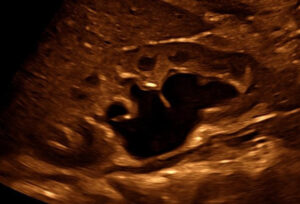

Pränatale kindernephrologische Beratung

Wird während der Ultraschalluntersuchungen in der Schwangerschaft eine Fehlbildung der Nieren, der ableitenden Harnwege oder eine andere Nierenerkrankung festgestellt, sind werdende Eltern oft verunsichert und besorgt. In solchen Situationen ist die fachliche Einordnung der Befunde durch eine eine Kinder-Nephrolog*in besonders wertvoll. Sie/er erklärt die Ergebnisse verständlich, bespricht mögliche Behandlungsschritte und unterstützt Eltern einfühlsam dabei, die Situation einzuordnen und die nächsten Schritte für die bestmögliche Betreuung ihres Kindes zu planen.